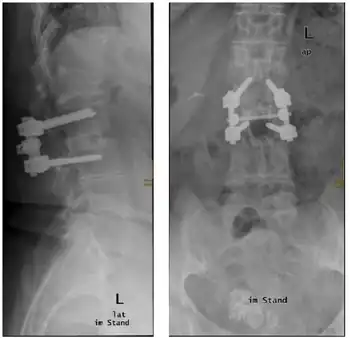

Due to the branches of the aorta that supply the anterior spinal artery, the most common causes are insufficiencies within the aorta. These include aortic aneurysms, dissections, direct trauma to the aorta, surgeries, and atherosclerosis. Acute disc herniation, cervical spondylosis, kyphoscoliosis, damage to the spinal column and neoplasia all could result in ischemia from anterior spinal artery occlusion leading to anterior cord syndrome. Other causes include vasculitis, polycythemia, sickle cell disease, decompression sickness, and collagen and elastin disorders.[1] A thrombus in the artery of Adamkiewicz can lead to an anterior spinal syndrome. This is the most feared, though rare complication of bronchial artery embolization done in massive hemoptysis.[6]

Treatment